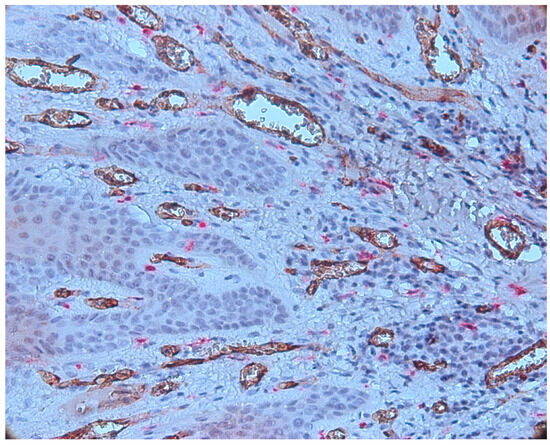

3.2. Mast Cells

3.3. Aspects of Microvessels

3.4. MCD and MVD